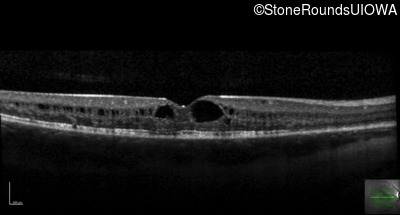

Optical Coherence Tomography - Right - 20/40 +1

Exemplar / OCT Stack

OCT Stack